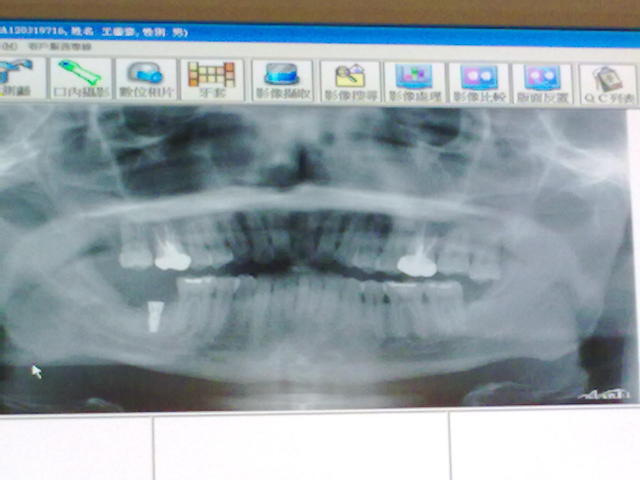

昨天下午 去植牙